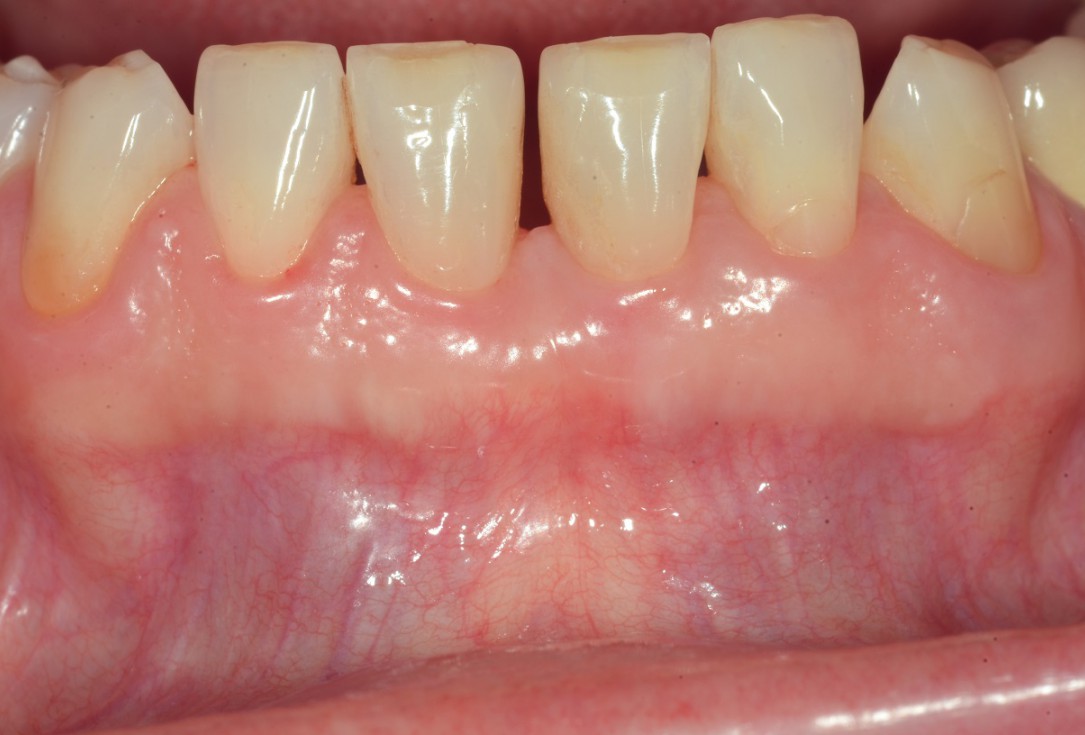

11/13 - Clinical situation 5 years post-operative.

Wide intrabony defect treated with the modified papilla preservation flap in conjunction with Straumann® Emdogain® and autogenous bone - Dr. B. Molnar